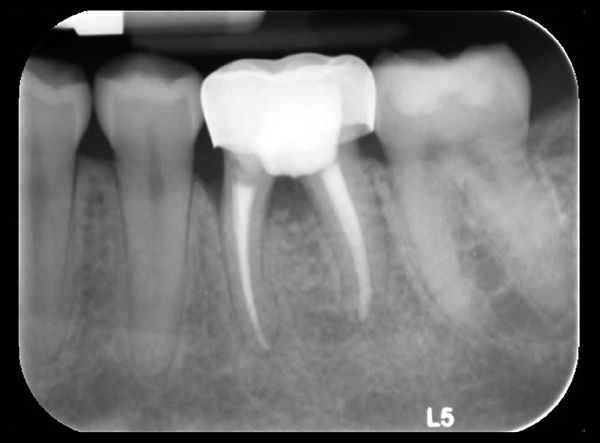

O 29 mm 1 o 33 mm 2 o 41 mm 2 o 48 mm. Straumannbone level tapered blt soft bone hard bone mandible in densifying mode make sure your osteotomy is 10 mm deeper than the actual implant final length. The straumann bone level tapered blt implant offers all the clinically proven features of the straumann bone level implant line plus the advantages of a tapered implant body. Implant blt straumann dental implant system.

Scs screwdrivers long and short 7. The straumann bone level implant line has a simple and consistent color coding and laser markings for quick and precise identification of secondary parts surgical instruments and auxiliaries. A unified color code simplifies identification of instruments and implants for the available endosteal diameters. 121 straumann standard implant the classic tissue level implant straumann standard implants have a smooth neck section of 28 mm and are especially suitable for classic.

In extreme hard bone utilize dac densify after cut protocol. Tissue level implants bone level implants. The shape surface and material combination are designed to deliver primary stability in all bone classes making the straumann bone level implant ideal for. Disposable saliva ejector and control pads 5.